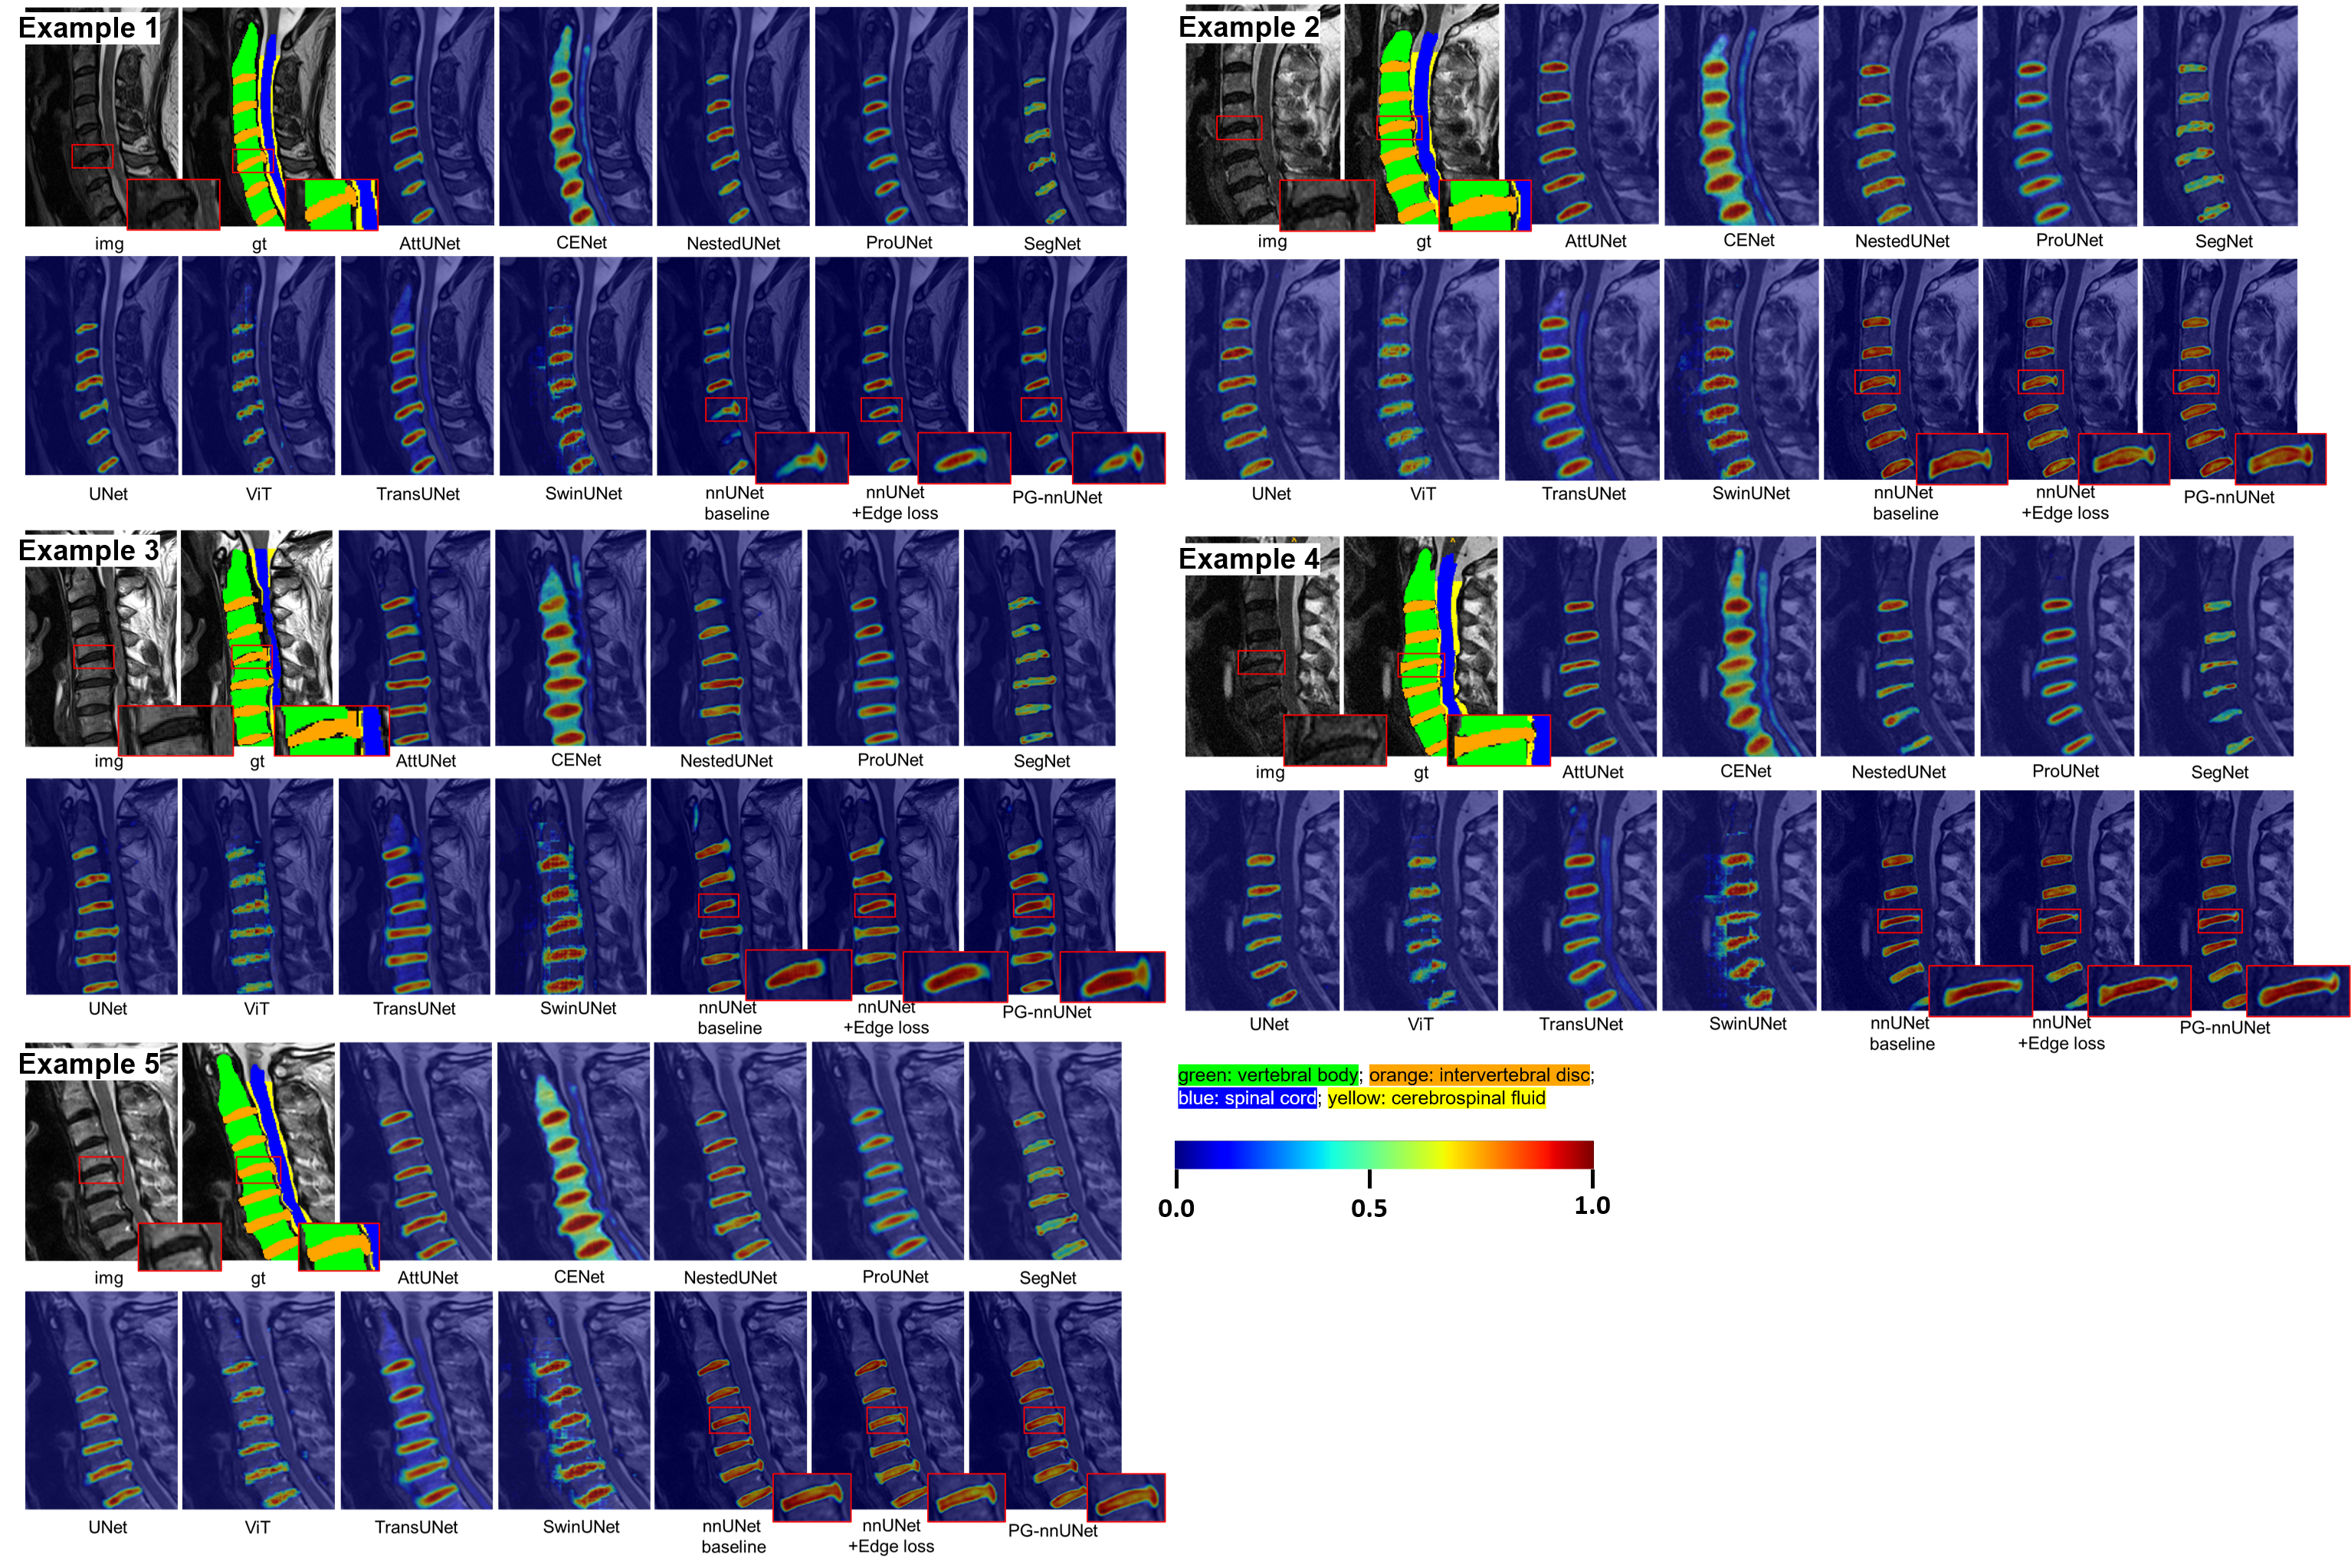

Figure 6 visualizes the segmentation predictions for several cases across different models. Example 1 and 2 highlight cases with T2 hyperintensity in the spinal cord (indicated by the red box), which is particularly challenging to predict accurately. Models such as CENet, NestedUNet, SwinUNet, and the nnUNet baseline failed to distinguish this region from CSF, and ProUNet incorrectly classified it as background. In contrast, nnUNet combined with edge loss and our proposed PG-nnUNet were able to accurately segment the region, thereby preventing errors in subsequent diagnoses. Example 3 and 4 show cases with ossification of the posterior longitudinal ligament (OPLL) (red box). Many models failed to segment the ossified region accurately (marked by blue arrows), likely due to differences in intensity compared to adjacent tissues. The nnUNet baseline even misclassified the ossification as part of the spinal cord in Example 3. However, our proposed PG-nnUNet performed well, effectively detecting these pathological regions and avoiding segmentation errors.

To further analyze the models’ performance, we visualized the class activation mappings (CAMs) using Grad-CAM++[8]. We specifically focused on the activation of intervertebral discs to assess model attention on disc herniations. As shown in Figure 7, some models, such as CENet, failed to activate the target regions accurately, while nnUNet-based models performed notably well. Compared to the nnUNet baseline, both nnUNet combined with edge loss and PG-nnUNet showed better attention to herniated areas. In Examples 1, 3, and 4, the herniated regions in PG-nnUNet were observably highlighted. This improvement stems from the proposed Pathology-Guided Detection Branch, which directs the model’s focus towards pathological areas. In contrast, other models struggled to distinguish herniations from disc regions, leading to a decrease in segmentation performance, particularly in these small, difficult-to-identify areas.

Refer to caption

Figure 6: Examples of cervical spine segmentation results and comparisons across different models. The red boxes indicate pathological areas, such as T2 hyperintensity in the spinal cord and ossification of the posterior longitudinal ligament (OPLL).

Figure 7: Visualization of the class activation mappings (CAMs) of intervertebral discs generated by Grad-CAM++[8]. The values are normalized to the range of 0-1. Regions with colors closer to 1 (hot colors) are more relevant to the segmentation results, while regions with colors closer to 0 (dark colors) are less relevant.